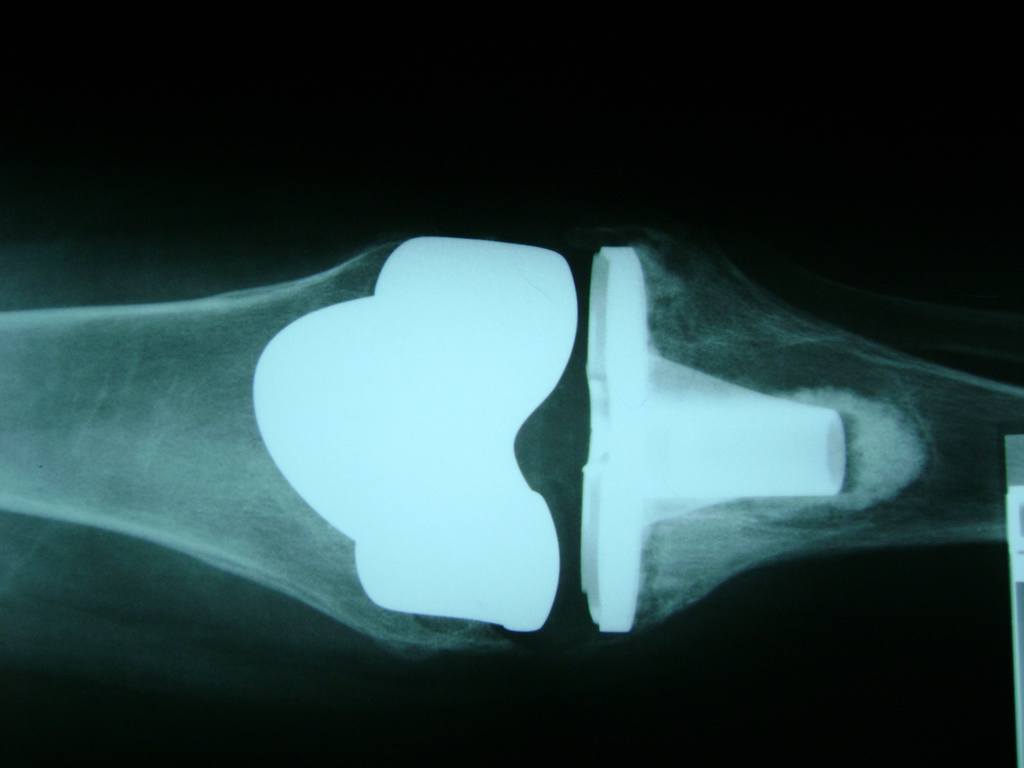

Fémur - Rodilla

La artroscopia de rodilla es un cirugía en el cual la estructura interna de la articulación es examinada ya sea para realizar un diagnostico o para realizar un tratamiento, este procedimiento se realiza utilizando un instrumento parecido a un pequeño tubo llamado artroscopio.

La artroscopia se popularizo en 1960 y hoy en día es muy común en todo el mundo. Típicamente, es realizada por cirujanos ortopédicos de manera ambulatoria. Cuando se realiza de manera ambulatoria los pacientes pueden regresar a casa después de la operación, no se requiere quedarse en hospital.